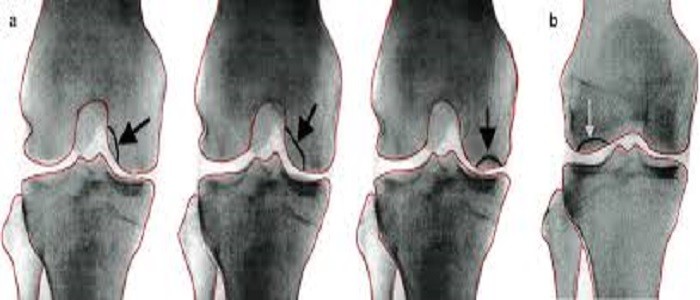

ما يحصل في مرض خشونة الرّكبة هو تحلُّل هذا الغضروف، ويحدث نتيجةً لذلك احتكاك العظمتين ببعضهما ممّا يُسبّب الشّعور بألم، وظهور انتفاخ، وتقليل مدى الحركة للرّكبة، وقد يُؤدّي في بعض الأحيان إلى تكوين نتوئات عظميّة. ويُعدّ التقدّم بالعمر أبرز عوامل الخطورة المُؤدّية للإصابة بخشونة الرّكبة، إلّا أنّها قد تُصيب الشّباب في حالات نادرةٍ خصوصاً إذا ما كان لديهم تاريخ عائليّ للإصابة بها، أو تعرَضوا لالتهاب أو ضرر في الرّكبة.

- ظهور تشوّهات في الشّكل الخارجيّ للرّكبة: وتتفاوت هذه التشوّهات مع درجة خشونة الرّكبة.